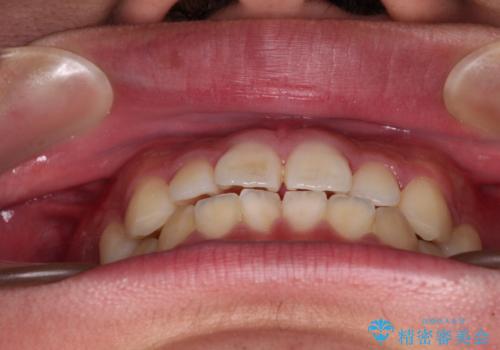

インビザライン・ライトは、製作できるアライナーの枚数に制限があるため、移動可能な量に限りがあります。

一方で、半年から1年程度で治療を終えることができるため、軽度の歯列不正の患者様には大変お勧めです。